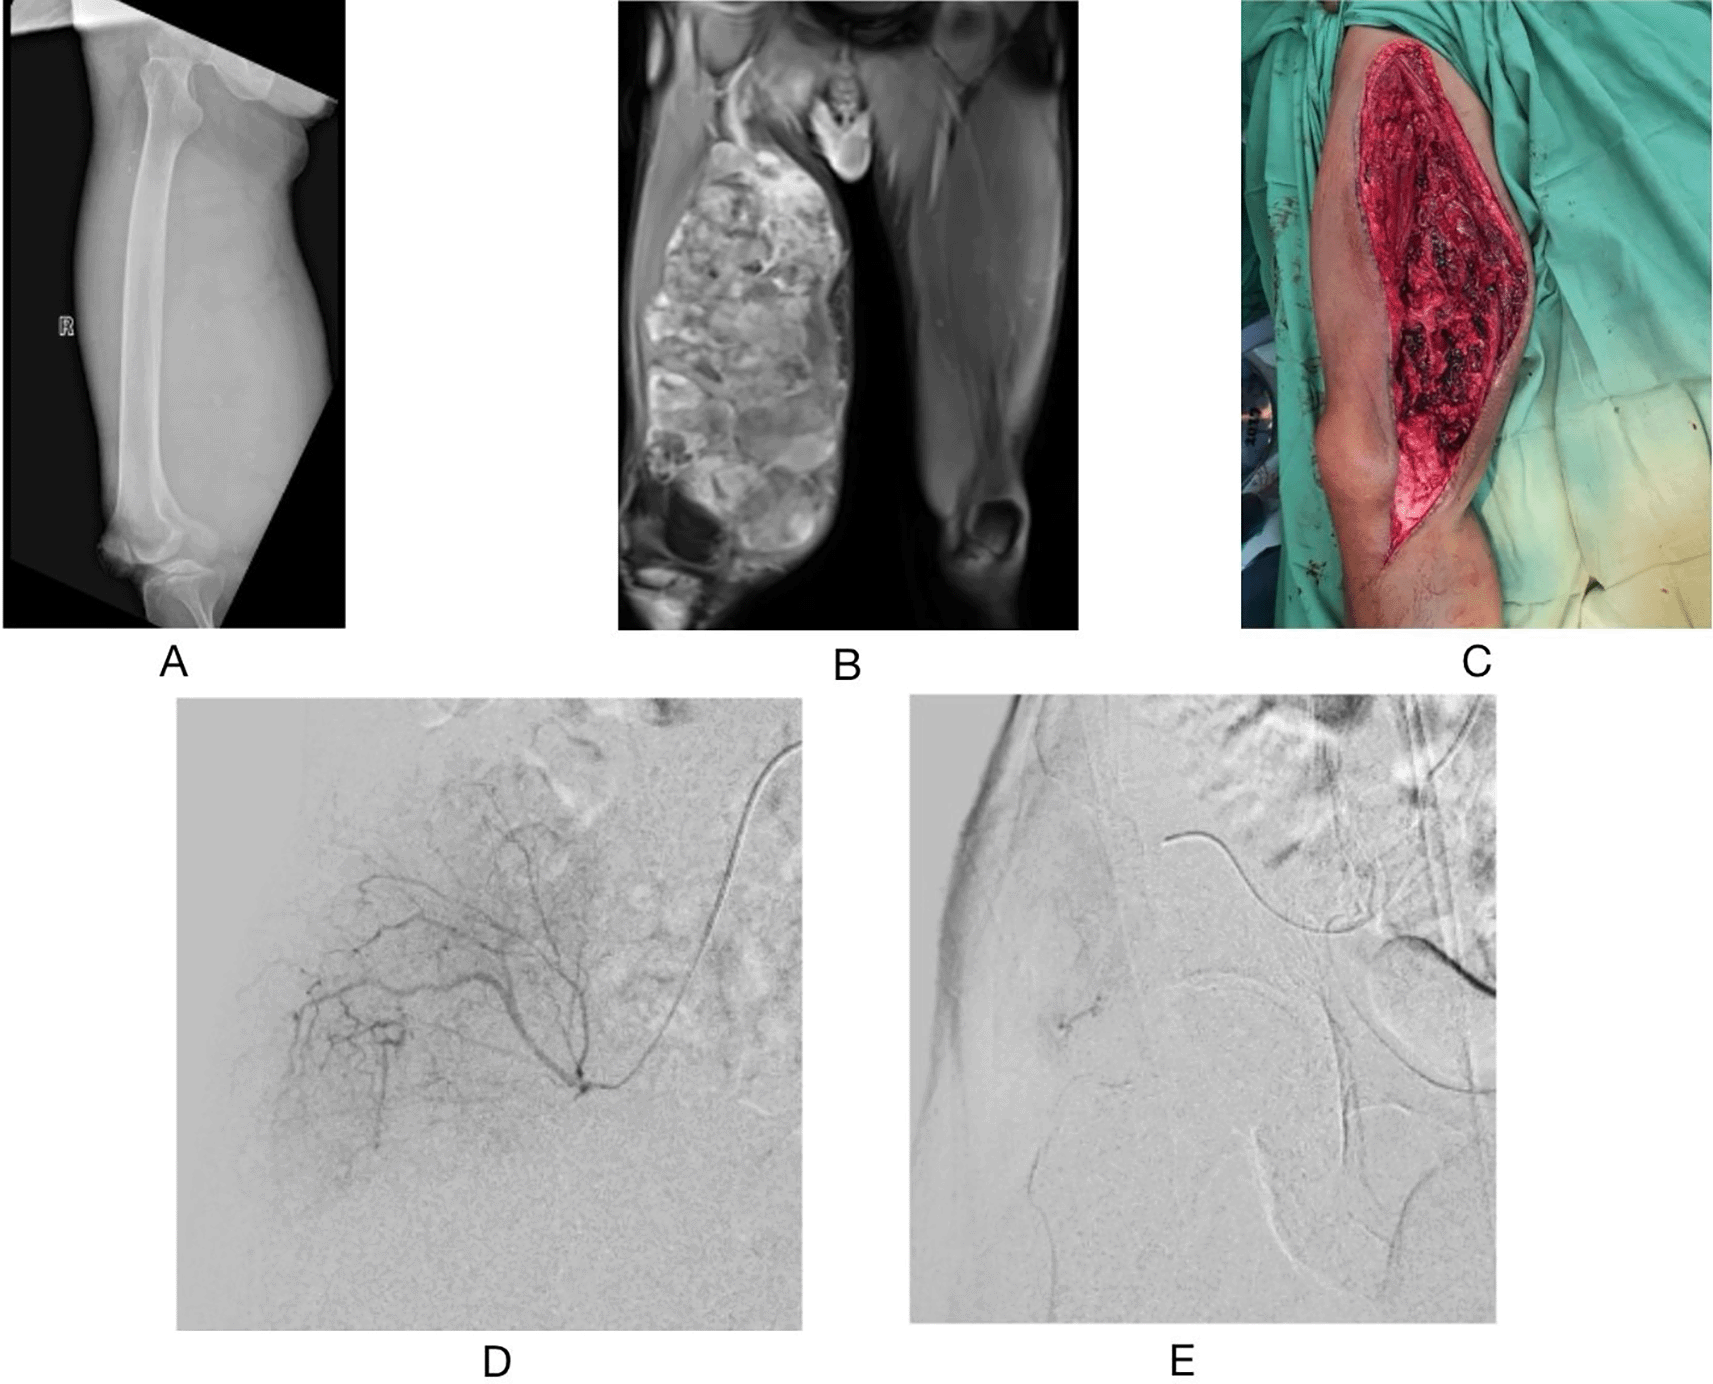

A 41-year-old man was referred for preoperative endovascular embolization a day prior to resection of a right femoral liposarcoma. Prior to the surgery, he had already undergone contrast MRI examination, which revealed a mixed heterogeneous mass with fat and soft tissue components involving all posterior and middle compartment femur muscle groups through almost all anterior muscle groups with no infiltration to the femur bone. Angiography revealed a hypervascular tumor stain with a feeding artery originating from the deep circumflex iliac artery. Following embolization with vertebral catheters, Progreat®, Gelfoam®, and bearing nsPVA® particles 355-500 μm, no hypervascularity was observed. Subsequently, the tumor was excised and 700 mL of blood was lost. The patient was then discharged on postoperative day 10. No recurrence was noted during the six months postoperative follow-up visit (Figure 3).

(A) preoperative right femur X-ray AP position (B) preoperative T1-weighted fat suppressed with mixed Gadolinium contrast enhancement (C) intraoperative picture (D) angiography before procedure (E) angiography evaluation after embolization procedure.